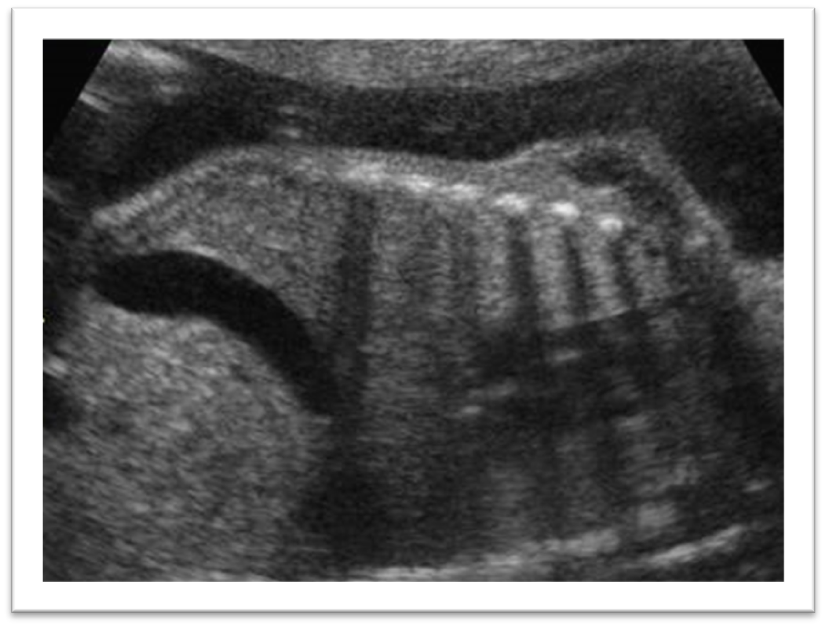

What are these images showing?

Bowel Obstruction

What are US finding for an obstructed bowel?

Multiple cystic structures, more than 2, proximal to site of atresia within abdomen discontinuous with stomach

Polyhydramnios is possible